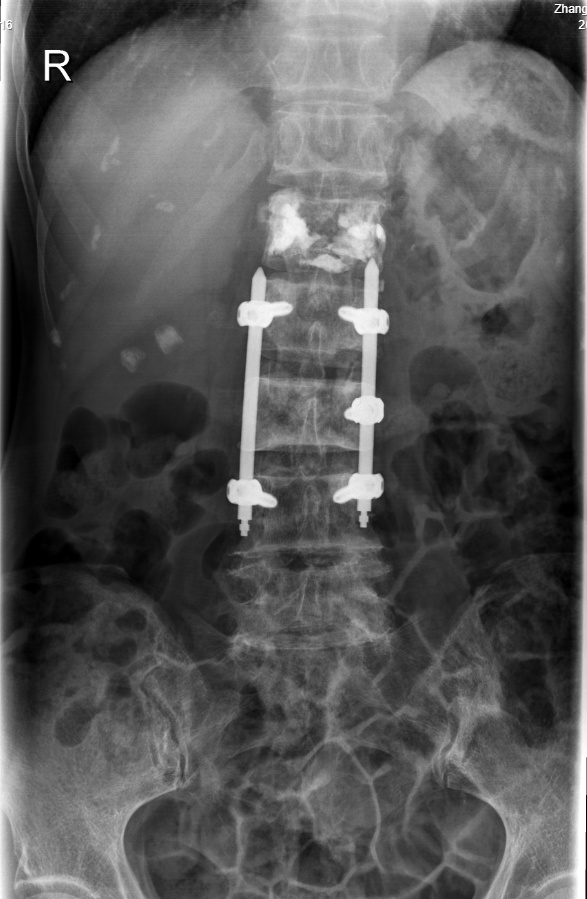

圖片7.png

磁共振提示:多發(fā)椎體及附件轉(zhuǎn)移瘤,其中腰1、3椎體骨質(zhì)破壞較明顯伴腰3椎管占位神經(jīng)受壓。

基于目前最新NOMS決策框架,需要根據(jù)每一位脊柱轉(zhuǎn)移瘤患者的全身情況選擇個(gè)性化的治療方式。由于患者Tomita評(píng)分8分(Tomita評(píng)分最高10分,評(píng)分越高,預(yù)后越差)、Tokuhashi評(píng)分2分(患者Tokuhashi總分0-8分地預(yù)期生存期不足6個(gè)月),經(jīng)住院檢查發(fā)現(xiàn)有低蛋白血癥及貧血,綜合評(píng)估其身體條件并不適合較大創(chuàng)傷手術(shù)。歐清彬副主任醫(yī)師團(tuán)隊(duì)與患者和家屬充分溝通后,決定為患者實(shí)施姑息性固定減壓手術(shù),即采用微創(chuàng)釘棒系統(tǒng)固定+部分椎板切除減壓以獲得即刻穩(wěn)定及解除神經(jīng)壓迫保護(hù)神經(jīng)功能。

圖片2.jpg

在“天璣”骨科手術(shù)機(jī)器人助力下,歐清彬副主任醫(yī)師團(tuán)隊(duì)順利完成“脊柱后路減壓內(nèi)固定+椎體強(qiáng)化+病理活檢穿刺術(shù)”,手術(shù)時(shí)長僅一個(gè)半小時(shí),精準(zhǔn)微創(chuàng)且高效。

圖片3.jpg

術(shù)后影像